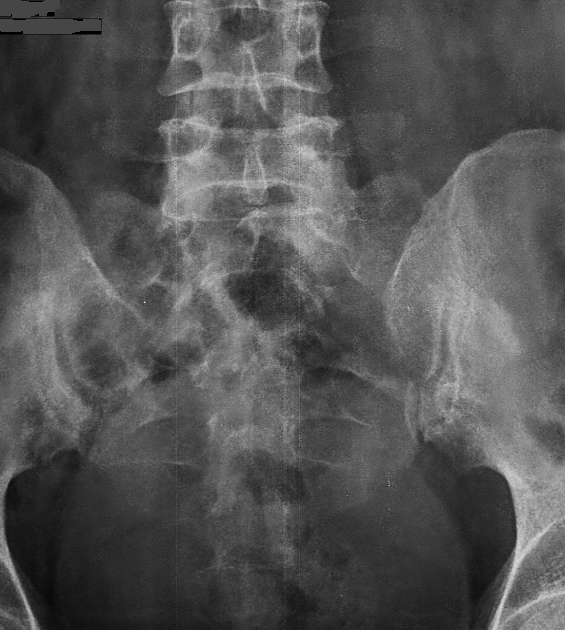

Figure 1 from Stress fracture of the sacrum Semantic Scholar Stress Fracture Sacrum Running sacral stress fractures occur more easily in people with bones weakened by osteoporosis, osteopenia, or nutrition problems, including deficiencies in calcium and vitamin d. manage sacral stress fracture with proper diagnosis and treatment. Patients typically report buttock pain, but also can report low back pain, groin pain, and muscle spasms. Low back pain is a common problem in. Stress Fracture Sacrum Running.